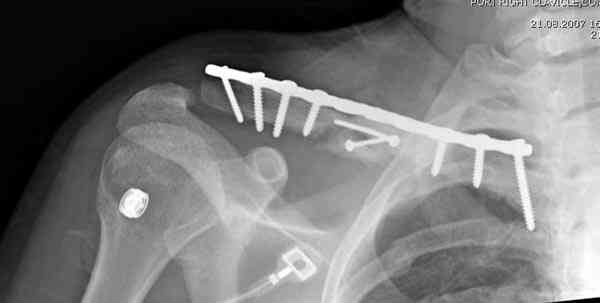

Недавно разбирали случай ложного сустава.

45 летная женщина после автоаварии, алкоголь 163 и 20 летним стажем курения.

Консервативное лечение, через 8 мес. операция Rockwood pin с костной пластикой в нашем городе другим врачом. После 8 недели падение, гвоздь удален оперирующим хирургом, больная направлена к нам. Фиксация реконструктивной пластиной с трикортикальным графтом, добавлен BMP-2. Для стабилизации фиксацию провели через акромион.

Вот уже два месяца больная также продолжает жаловаться на боли, буквально на днях удалили акромиальную часть пластины с специальной пилой с алмазным покрытием для медицинского металла. До сих пор судьба ложного сустава неизвестна....